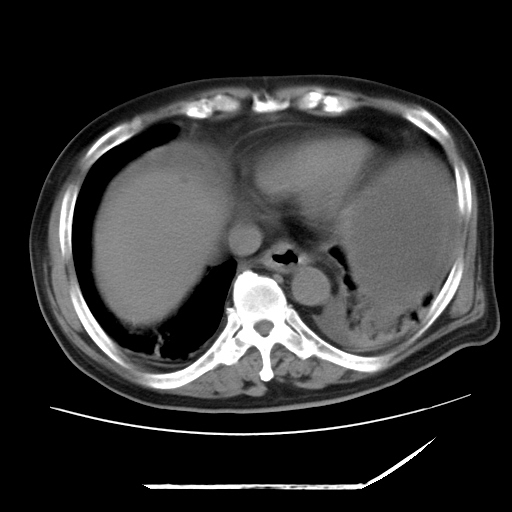

以下是引用zxl51642在2009-8-12 18:55:00的发言:[br]1、肠系膜脂肪浑浊,密度增高,腹水,支持腹膜炎诊断;2、右肾盂及输尿管中段结石,左输尿管起始段结石;3、胆囊切除术后改变?4、双侧胸膜腔少量积液;5、胰腺体积不大,勾勒清楚,肾前筋膜无增厚,不支持胰腺炎,请结合血尿淀粉酶及临床。